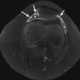

Arthritis with joint effusion

A joint effusion is the presence of increased intra-articular fluid. It may affect any joint. [Source: Wikipedia ]